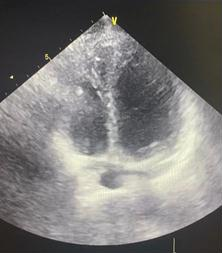

Transthoracic echocardiography (Fig. 3) confirmed preserved left ventricular systolic function ( left ventricular ejection fraction 58%) but demonstrated a markedly small RV, measuring only 20 mm in basal diameter and 48 mm in longitudinal length. According to ASE/EACVI reference values, the normal basal RV diameter in adults is 25–41 mm (mean 33 (4) mm) and the longitudinal length is 59–83 mm (mean 71 (6) mm). In our patient, the z-scores for basal diameter and length were −3.25 and −3.83, respectively, corresponding to below the 1st percentile. These findings confirm an exceptionally small RV creating unique technical challenge for device implantation.

Figure 3. Transthoracic echocardiographic image demonstrating a small right ventricular cavity